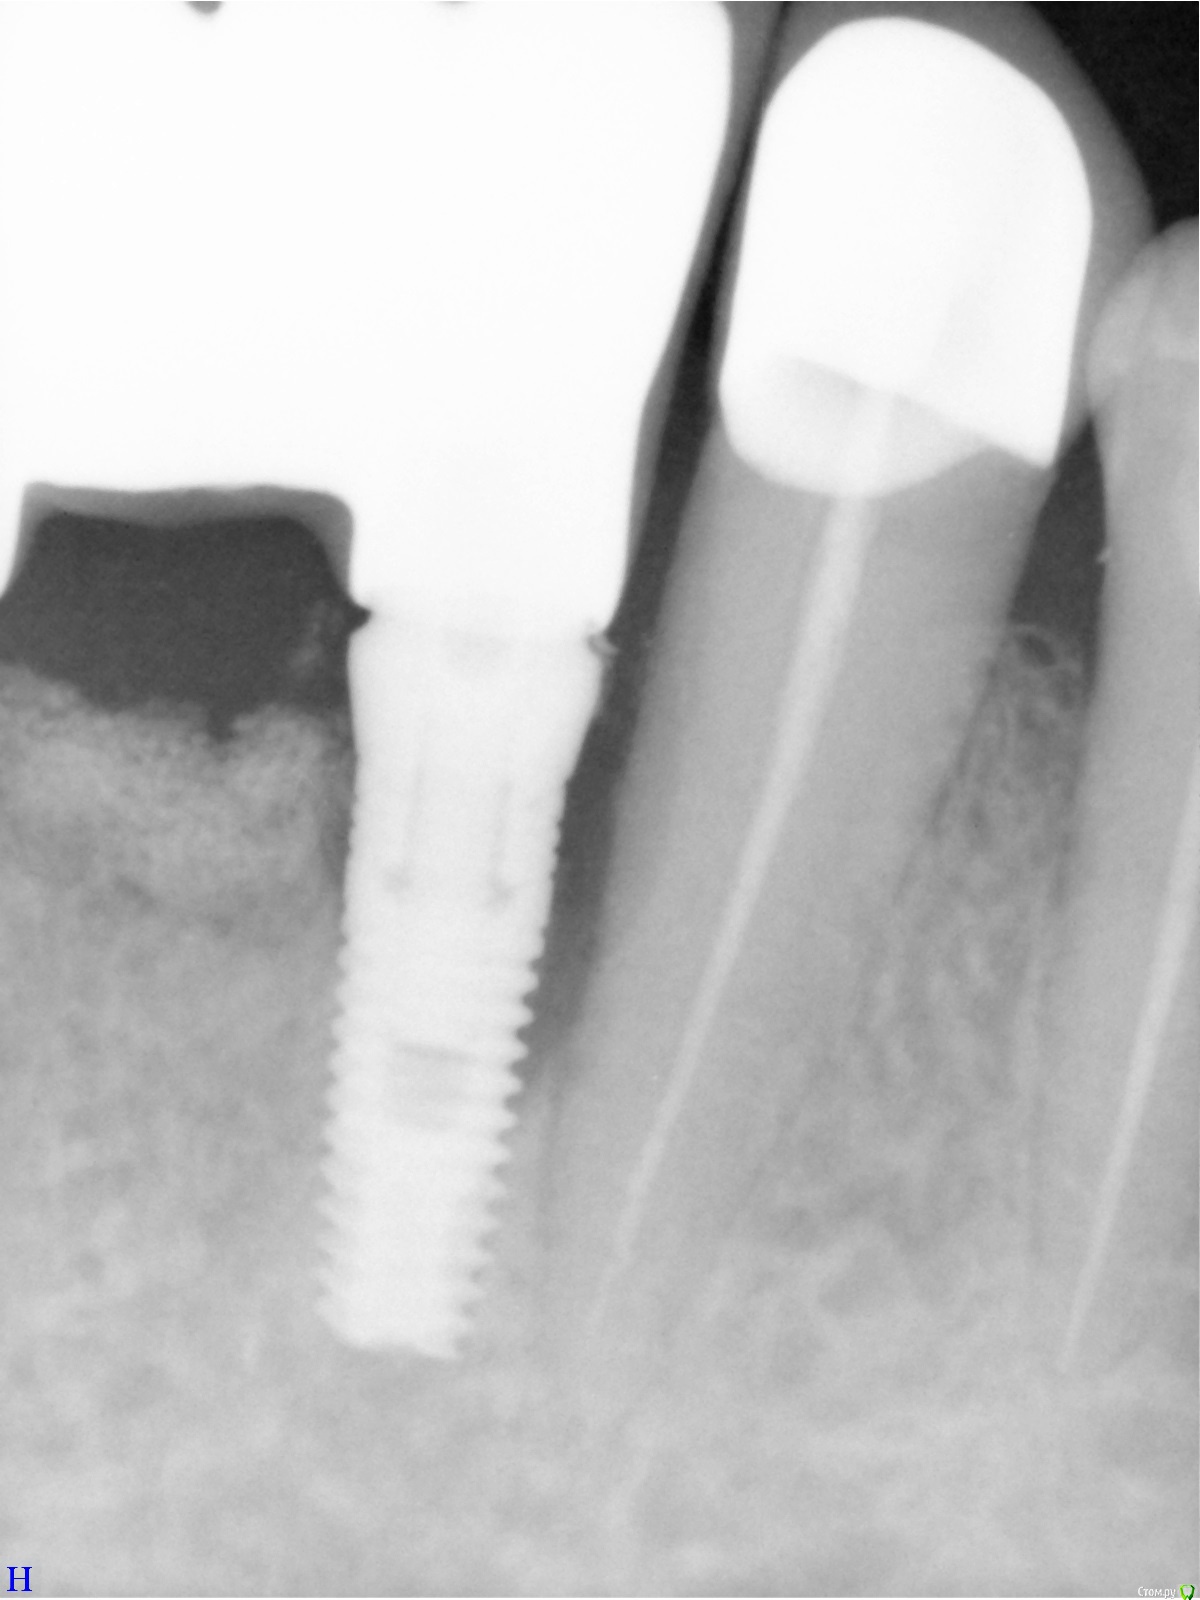

Dantist55 Опубликовано 10 мая, 2015 Поделиться Опубликовано 10 мая, 2015 (изменено) Коллеги как считаете, что могло послужить причиной периимплантита? Винт Альфа-био, под нагрузкой 3 мес. До протезирования все было стабильно. Изменено 10 мая, 2015 пользователем Dantist55 Ссылка на комментарий

Bier Опубликовано 10 мая, 2015 Поделиться Опубликовано 10 мая, 2015 А сами не видите что ли? Недосад коронки + полкило цемента под десной 2 Ссылка на комментарий

Большой Зеленый Опубликовано 10 мая, 2015 Поделиться Опубликовано 10 мая, 2015 А сами не видите что ли? Недосад коронки + полкило цемента под десной+1 Да и близковато к зубу Ссылка на комментарий

chervoncevdaniil Опубликовано 10 мая, 2015 Поделиться Опубликовано 10 мая, 2015 Коллеги как считаете, что могло послужить причиной периимплантита? Винт Альфа-био, под нагрузкой 3 мес. До протезирования все было стабильно.Надеюсь что ортопед-не вы,косяк 100% ортопедический Ссылка на комментарий

syrovovec Опубликовано 10 мая, 2015 Поделиться Опубликовано 10 мая, 2015 Да и близковато как бы к зубу 1 Ссылка на комментарий

CToMaToJlor Опубликовано 11 мая, 2015 Поделиться Опубликовано 11 мая, 2015 (изменено) Немного отличное мнение: слишком близко к зубу и не выдержали сроки после НКР.( ведь было нкр? Не более 4 месяцев ждали?) мое мнение: даже самая ужасная ортопедия за 3 месяца не даст такой убыли. Изменено 11 мая, 2015 пользователем CToMaToJlor Ссылка на комментарий